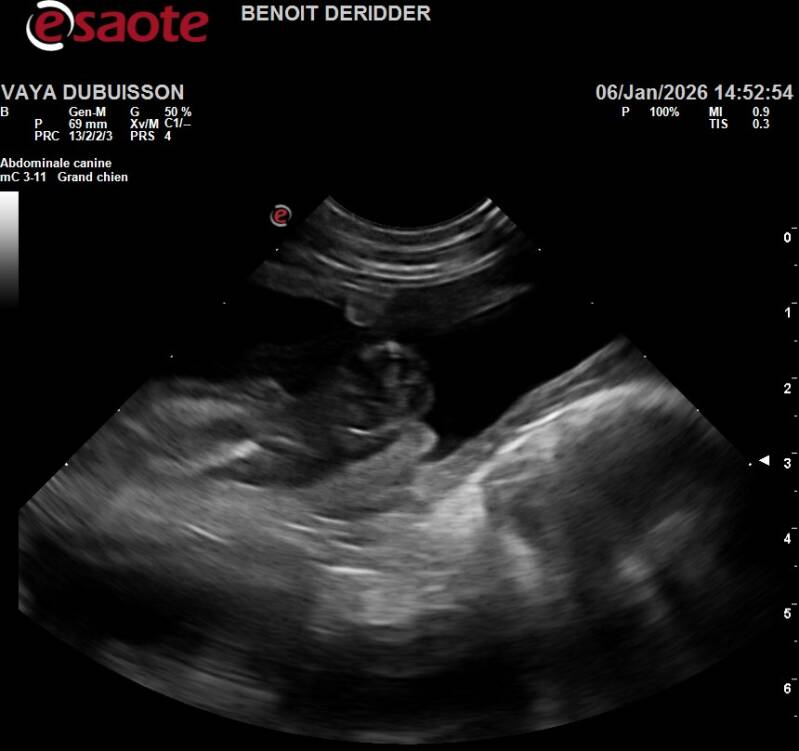

Ce 06/01/2026, je suis allée chez le veto pour une échographie afin de confirmer la gestation de Vayana mais à coup sûr, j'en étais convaincue parce que Vasco & Vayana c'est magique, je dirai même plus une alchimie, ils ne leur suffit qu'un seul accouplement pour que la magie opère..

Ça y est, Benoît commence à passer sur le ventre de Vayana et nous pouvons apercevoir sur l'écran jouxtant en hauteur de la table quelque chose ou ressemble à ... Oui oui dit-il avec un sourire joviale, Vayana a remis ça, on en compte approximativement 7 mais connaissant la demoiselle, nous ne serions pas surpris d'en avoir 10...